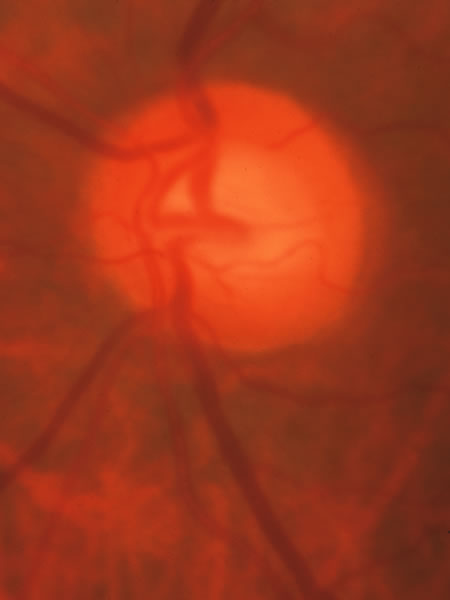

In acute angle-closure glaucoma (Fig. 33), the optic disc may swell,147–149 perhaps as a result of ischemia, but because of corneal edema and preoccupation with the angle status, it is not often seen. Even after an attack lasting several days, there is often no visual loss; the disc may remain normal appearing or may develop some degree of pallor resembling that of nonglaucomatous optic atrophy.150–152 Excavation of the disc does not seem to result from an acute attack but may result from persistent residual pressure elevation after the attack. If excavation is already present at the time that a patient presents with symptomatic angle closure, the cupping is evidence that for some time an asymptomatic, perhaps gradual, rise of intraocular pressure elevation preceded the abrupt onset of symptoms.

Fig. 33. Swollen disc tissue during an acute attack of angle closure glaucoma.